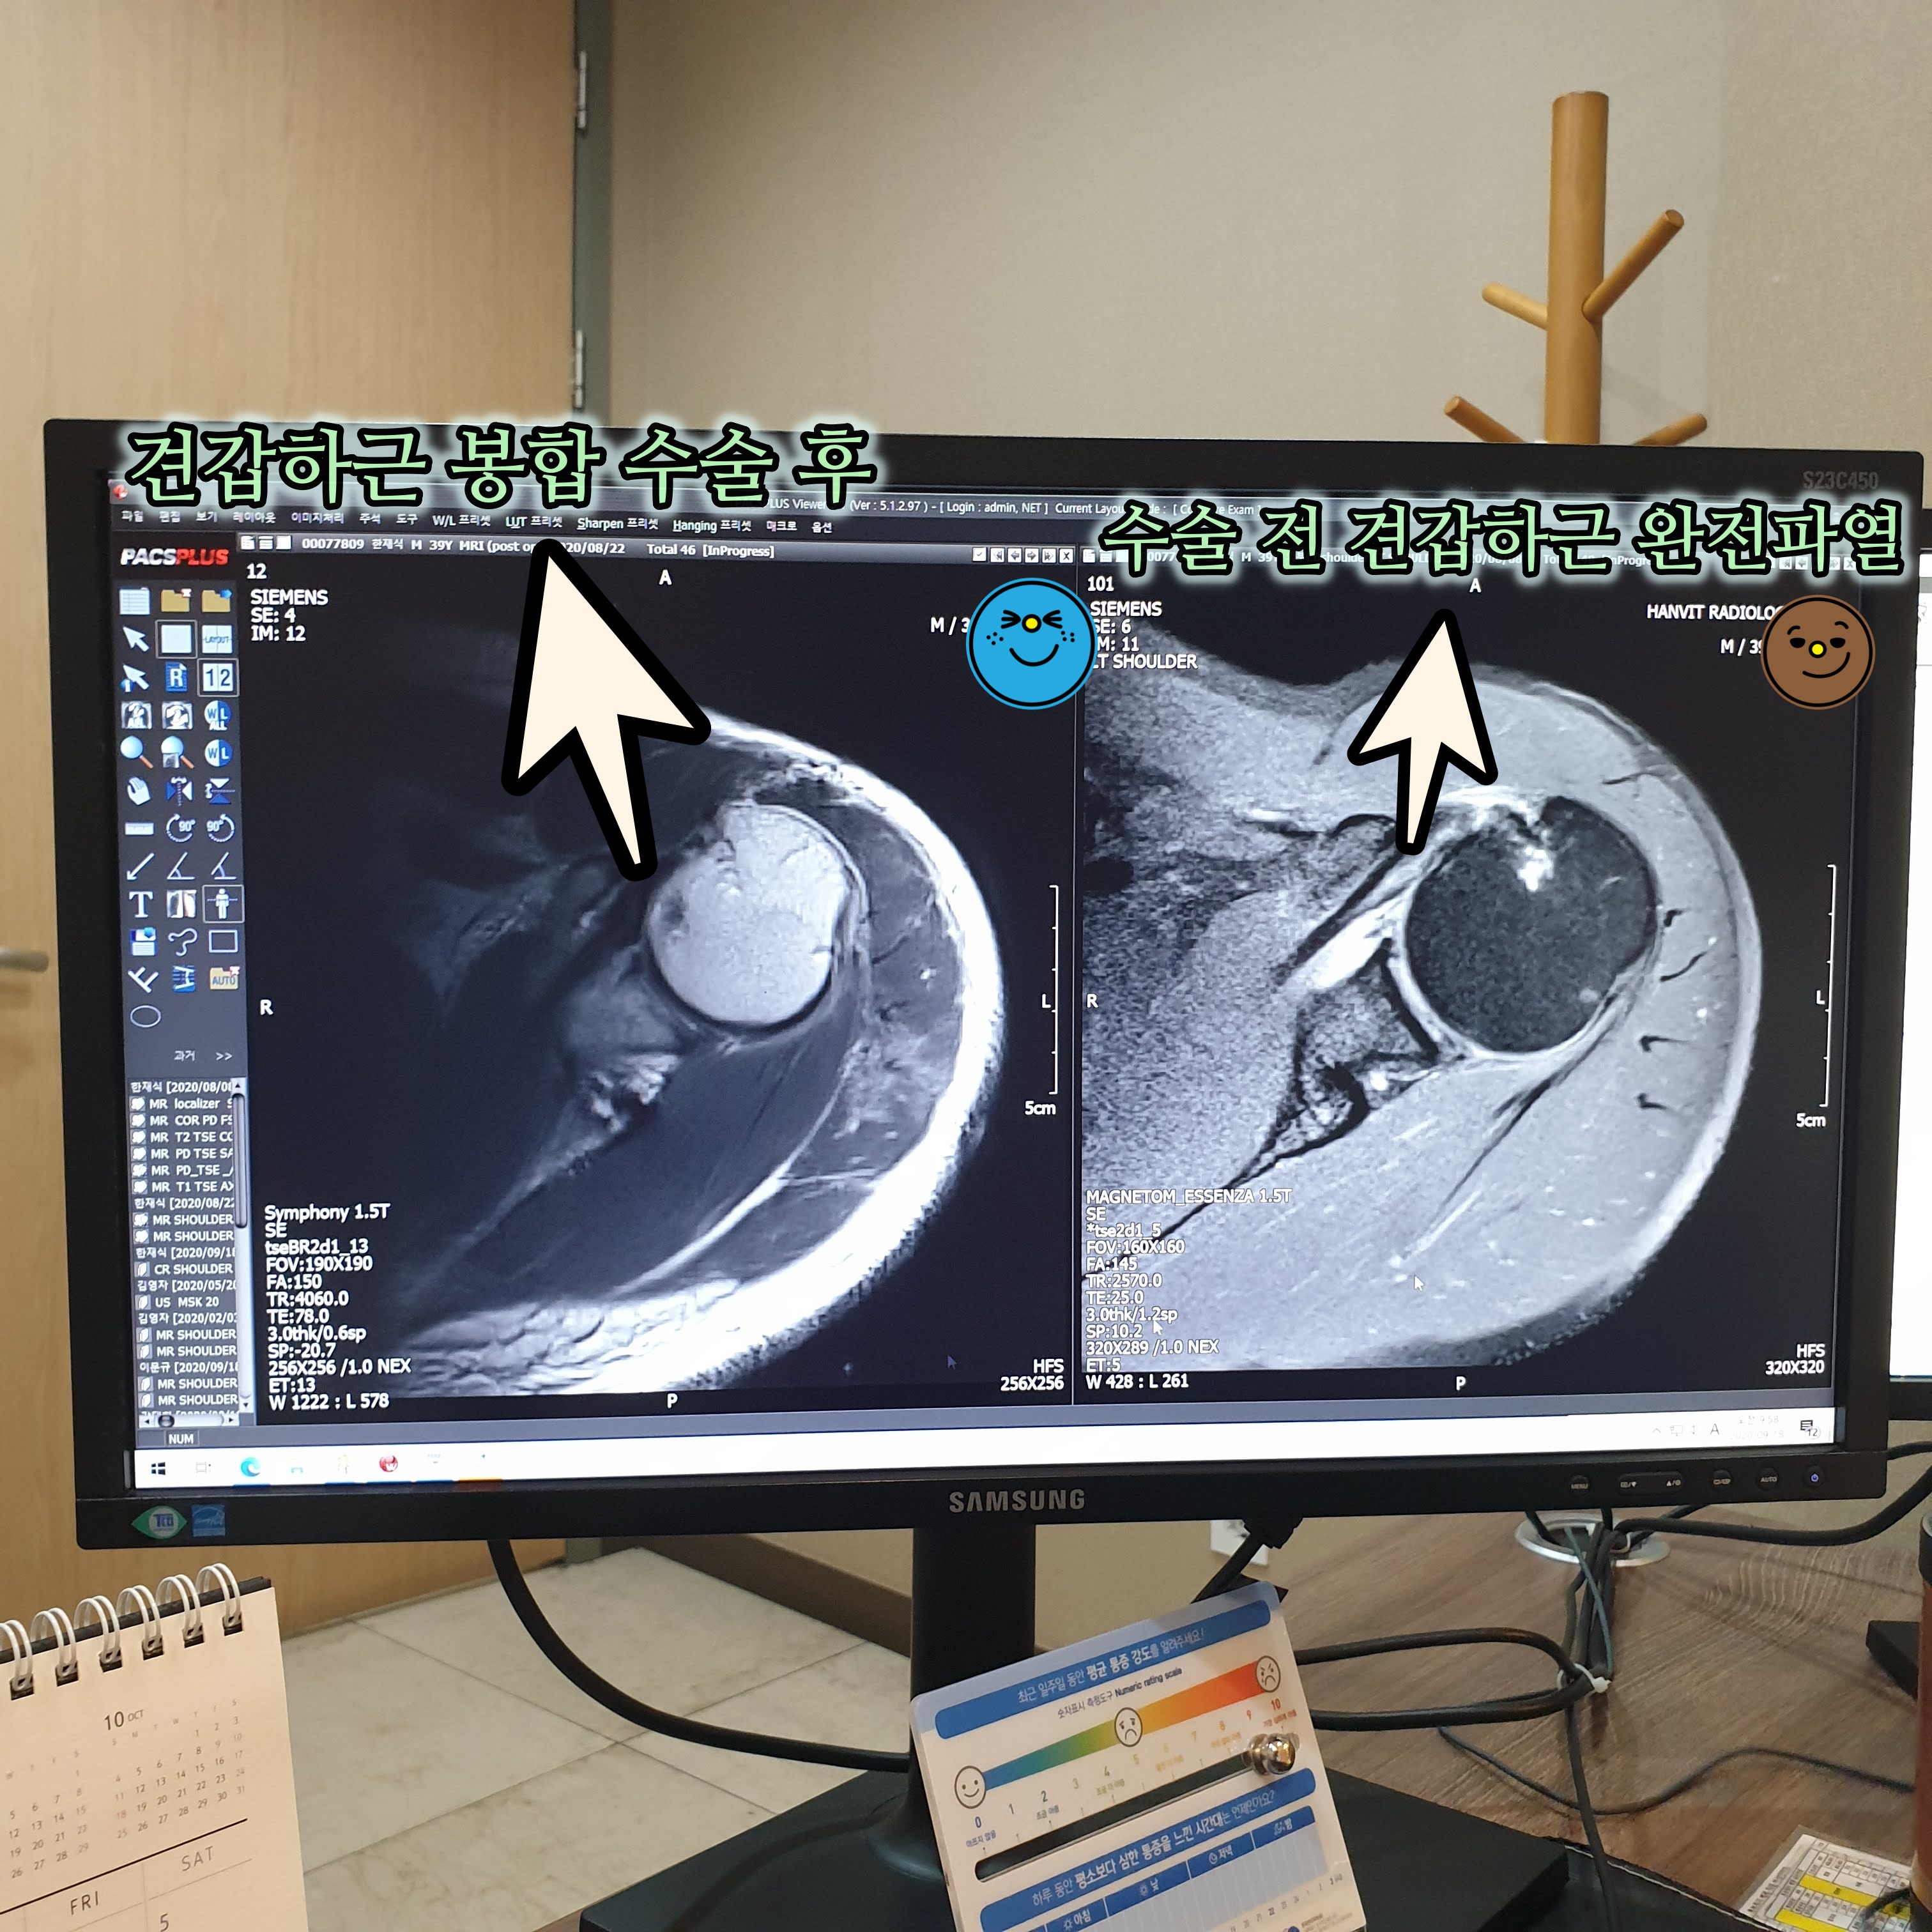

당시 수술 전 후 mri 사진이다. mri에서 힘줄 부분은 검고 납작해야 건강한 것인데 수술 전 견갑하근 부위를 보면 파열이 되어 하얗게 나타나는 것을 확인 할 수 있다. 수술 후 찍은 mri 사진에서는 봉합한 부분이 까맣게 나타나는 것이 보인다. 원장님의 진료에 따라 보호대 착용 잘하고 재활 단계도 착실하게 진행을 하니 수술 부위가 잘 붙어 결국에는 성공적인 수술이었다. 당시 왼쪽 어깨 수술 후 4주간은 보호대를 착용하여 움직임을 제한시켰고, 6개월 간 되도록 왼쪽 어깨를 쓰지 않으려 노력했는데 그러다보니 보상작용으로 오른쪽 어깨에 이상이 온 것을 느끼게 되었다. 6개월째에 수술 검사를 듣고 새롭게 오른쪽 어깨가 아파 다시 mri를 찍었었다.